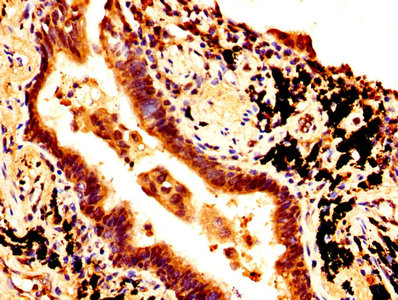

IHC image of CSB-PA16539A0Rb diluted at 1:500 and staining in paraffin-embedded human breast cancer performed on a Leica BondTM system. After dewaxing and hydration, antigen retrieval was mediated by high pressure in a citrate buffer (pH 6.0). Section was blocked with 10% normal goat serum 30min at RT. Then primary antibody (1% BSA) was incubated at 4°C overnight. The primary is detected by a biotinylated secondary antibody and visualized using an HRP conjugated SP system.